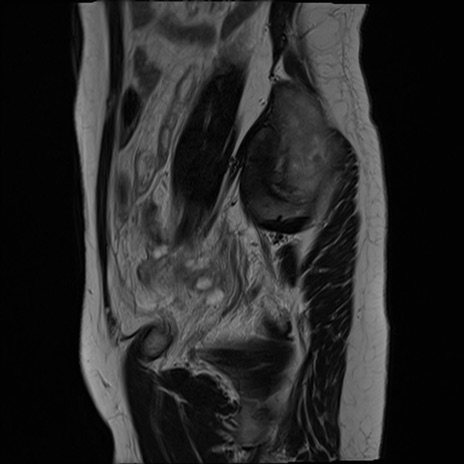

症例39 T2WI(矢状断像)

MRI(4日後)